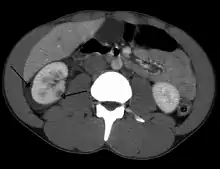

| Abdominal trauma resulting in a right kidney contusion (open arrow) and blood surrounding the kidney (closed arrow) as seen on CT | |

The kidneys may also be injured; they are somewhat but not completely protected by the ribs.[6] Kidney lacerations and contusions may also occur.[13] Kidney injury, a common finding in children with blunt abdominal trauma, may be associated with bloody urine.[13] Kidney lacerations may be associated with urinoma or leakage of urine into the abdomen.[4] A shattered kidney is one with multiple lacerations and an associated fragmentation of the kidney tissue.[4]